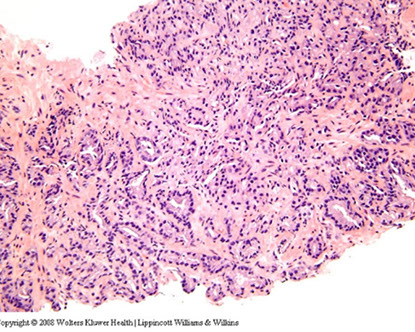

Ductal Adenocarcinoma

Hard to diff HG-PIN and ductal AC

- ductal ACs are agressive, advanced stage, and assoc c a poor px

- critical to diff from PIN

- ductal AC usually centrally located in periurethral region and sampled on TURP

-- PIN uncommon in periurethral region and infreq seen on TURP

- ductal AC usually has true papillary fronds c well-formed fibrovascular core, whereas HG-PIN more freq reveals micropapillary fronds c tall columns of epithelium w/o fibrovascular stalks

- ductal AC freq has comedonecrosis, which can be extensive

-- HG-PIN lacks comedonecrosis

- ductal AC can consist of large or back-to-back glands, whereas glands c PIN are of the size and distribution of b9 glands

- use of basal cell markers in the DDx can be problematic as both HG-PIN and ductal AC can have a patchy basal cell layer, however, the lack of a basal cell layer in numerous glands rules out PIN

Although the MC forms of ductal AC mimic cribriform and micropapillary HG-PIN, ductal AC can be composed of simple glands lined by stratified columnar epithelium c cytologic and architectural features of flat and tufting HG-PIN

- these PIN-like ductal cancers are distinguished from HG-PIN either bc the atypical glands are too crowded to represent HG-PIN or there are too many atypical glands that are negative for basal cell markers to be consistent with HG-PIN

- additional differences are in the PIN-like ductal AC, many of the glands are lined by flat epithelium (an uncommon pattern in HG-PIN) and the glands are often cystically dilated

Px: up to 1/2 metastatic at dx

Ductal AC